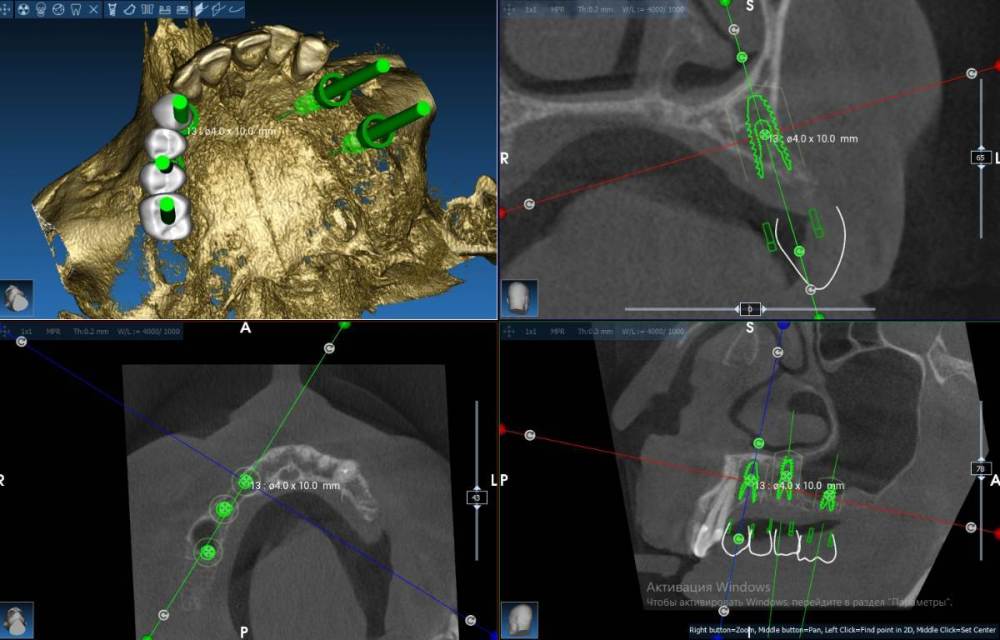

Fin Опубликовано 2 августа, 2022 Поделиться Опубликовано 2 августа, 2022 (изменено) Здравствуйте коллеги. Очень нужен ваш совет с планом лечения. Планирую установить 4 импланта на В.Ч.. В области зубов 2.4 и 2.6 все более менее понятно( 2.4 просто ставить а 2.6 ОСЛ и ставить), а вот в 1 сегменте все значительно сложнее. На данный момент имею три варианта конечно все варианты с навигационным шаблоном: 1.) 1.3 +НКР титановой сеткой (смущает что восстанавливать надо небно) 1.5 под углом и протезом на МЮ с небольшой консолью 1.6 (в виде премоляра) 2. 1.3 все так же либо рискнуть и оставить пару витков открытыми 1.5 имплант 4х10(11,5) и 1.7- 4х 7,3 с ЗСЛ 3 . Может Все таки пора начинать ставить анкилоз и поставить в обл 1.3 3,5х8 с небольшим оголением небной стенки.В остальный местах на этой стороне так же ануилоз. Протезрование делать с уровня МЮ. Благодарю Вас за советы. Скрины 2 сегмента Изменено 2 августа, 2022 пользователем Fin Ссылка на комментарий

Fin Опубликовано 2 августа, 2022 Автор Поделиться Опубликовано 2 августа, 2022 (изменено) 1 час назад, АнтонТЛТ сказал: @Fin сделайте расстановку зубов, исходите из положения ортопедического, а не условий костной ткани Вы правы...Быстро сделал виртуально постановку, нужно наращивать с обеих сторон получается Изменено 2 августа, 2022 пользователем Fin Ссылка на комментарий

АнтонТЛТ Опубликовано 2 августа, 2022 Поделиться Опубликовано 2 августа, 2022 А теперь коронку по торку наклоните, чтобы рвущий бугор клыка был на одной дуге с режущим краем 12 и вестибулярного бугра 14 Ссылка на комментарий

Irouil Опубликовано 2 августа, 2022 Поделиться Опубликовано 2 августа, 2022 (изменено) Во первых я бы взял винт 3.6 Во вторых на этом скрине вроде бы нужно как раз небнее, так выход практически в бугор В третьих исходя из первых двух пунктов + конденсация вестибулярно все должно быть нормально В четвертых пятёрку бы дистальнее P.S. да, насчёт бугра Антон прав, он завален Вообще, все эти расстановки без макетирования на моделях меня немного смущают всегда Изменено 2 августа, 2022 пользователем Irouil 1 1 Ссылка на комментарий

АнтонТЛТ Опубликовано 2 августа, 2022 Поделиться Опубликовано 2 августа, 2022 Короче качайте экзокад с торрента и учитесь расставлять зубы с учётом прикуса. Тогда вопросов по позициям имплантатов будет меньше. Или кт в прикусе с захватом антагонистов. Но надёжнее первый вариант. Ссылка на комментарий

Fin Опубликовано 2 августа, 2022 Автор Поделиться Опубликовано 2 августа, 2022 (изменено) 37 минут назад, АнтонТЛТ сказал: Короче качайте экзокад с торрента и учитесь расставлять зубы с учётом прикуса. Тогда вопросов по позициям имплантатов будет меньше. Или кт в прикусе с захватом антагонистов. Но надёжнее первый вариант. Большое спасибо. Не знал что экзокад есть на торентах, буду искать. Компьютер достаточно современный любой пойдет. Да Клык завалил (вечно тороплюсь). Антагонистов на данный момент нет, делаю времянки из металло-пластмассы. 46 минут назад, Irouil сказал: Во первых я бы взял винт 3.6 Во вторых на этом скрине вроде бы нужно как раз небнее, так выход практически в бугор В третьих исходя из первых двух пунктов + конденсация вестибулярно все должно быть нормально В четвертых пятёрку бы дистальнее P.S. да, насчёт бугра Антон прав, он завален Вообще, все эти расстановки без макетирования на моделях меня немного смущают всегда Большое спасибо Вам за ответ, постараюсь в близжайшее дни сделать воск и совместить с КТ. 3,6 нет есть 3.5, но меня вечно пугает риск перелома 3.5 у корейцев поэтому и заговорил о другой системе. Изменено 2 августа, 2022 пользователем Fin Ссылка на комментарий